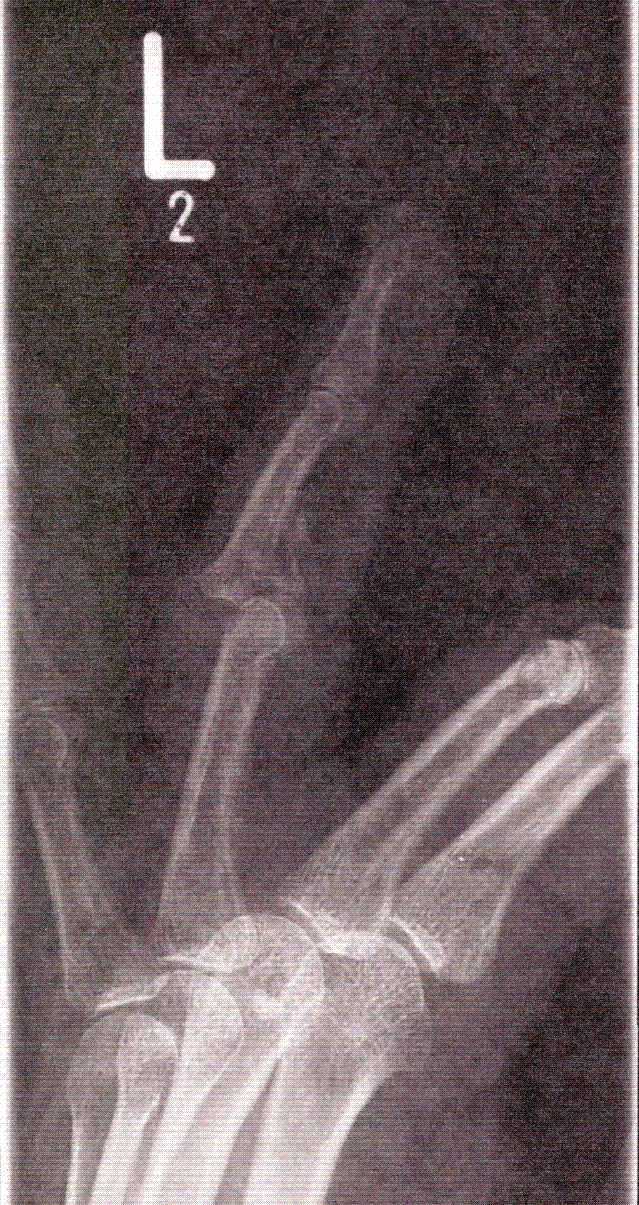

Die Unfallröntgenaufnahme zeigt eine Mittelgliedbasisfraktur des 4. Finger links mit Luxation des Hauptfragmentes und seiner Gelenkfläche nach dorsal